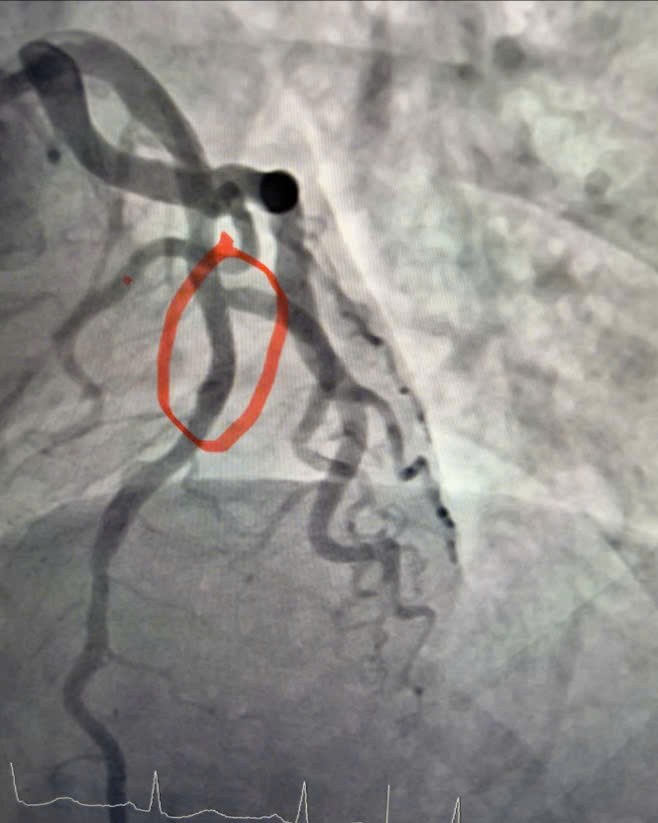

Hình ảnh động mạch vành sau can thiệp đặt stent, dòng máu nuôi cơ tim được tái thông tốt.

Ê-kíp bác sĩ Khoa Nội Tim mạch đã tiến hành chụp động mạch vành, kết quả cho thấy động mạch liên thất trước đoạn 1 – nhánh thủ phạm gây nhồi máu – bị hẹp tới 95%. Người bệnh được can thiệp nong và đặt stent động mạch vành, giúp tái thông dòng máu nuôi cơ tim, hạn chế tối đa tổn thương cơ tim và các biến chứng nguy hiểm.

Sau can thiệp, dòng chảy mạch vành được tái thông tốt, tình trạng người bệnh ổn định, triệu chứng đau ngực giảm rõ rệt và tiếp tục được theo dõi, điều trị theo phác đồ chuyên môn về bệnh mạch vành cấp.